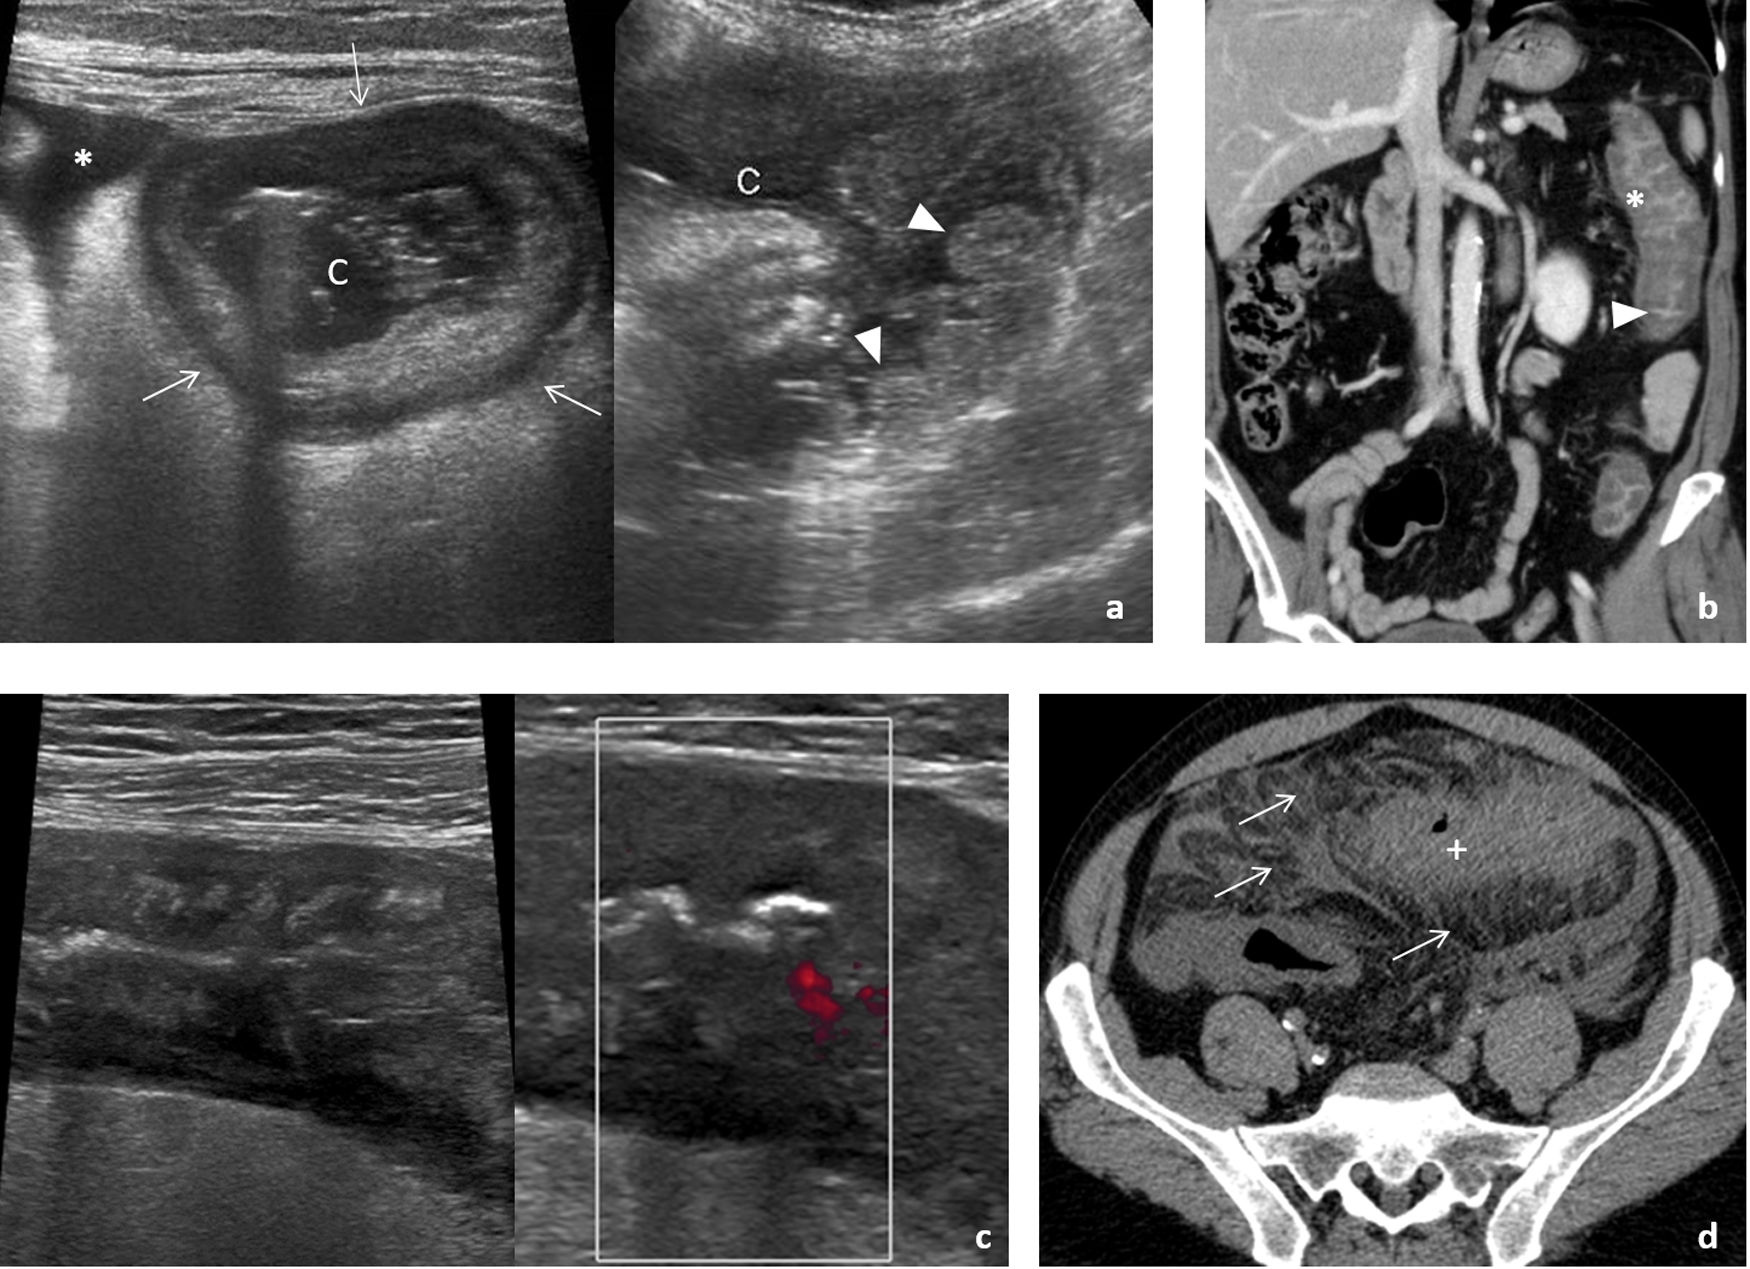

Consecuencia de la ingesta de la larva del parásito en pescado crudo o poco cocinado; aunque los primeros casos se describen en países asiáticos, se ha globalizado. Cuando, como ocurre habitualmente, afecta al estómago, la sintomatología aparece en menos de 24 horas. Provoca intenso dolor agudo en epigastrio, náuseas y vómitos, pudiendo simular patología pancreatobiliar. La ecografía, muchas veces urgente, muestra un importante engrosamiento difuso de la pared gástrica (fig. 1A) y ascitis, planteando diagnóstico diferencial con patología tumoral (linfoma o adenocarcinoma difuso) o gastritis eosinofílica (fig. 1B).

Afectación infecciosa del estómago. A-C) Primer caso de paciente que acude a urgencias por dolor intenso en epigastrio, con náuseas y vómitos abundantes de pocas horas de evolución, por el que se solicita ecografía urgente (A). Engrosamiento circunferencial y simétrico (flechas finas) de la pared de cuerpo y antro gástrico, que se correlaciona con las imágenes de tomografía computarizada (TC) en incidencia axial (B) y reconstrucción coronal (C) que se realizó a continuación, donde predomina un engrosamiento hipodenso (*) que orienta a edema submucoso. Con la sospecha de cuadro inflamatorio sin poder descartar otras causas, el paciente es sometido a endoscopia que muestra engrosamiento de pliegues gástricos y eritema mucoso con el resultado histológico en la biopsia de gastritis crónica superficial con eosinofilia, muy sugerente de gastritis por anisakis, aunque no pudo identificarse el parásito. El cuadro se resolvió en pocos días con tratamiento sintomático. D y E) Segundo caso de paciente que refiere dolor epigástrico de semanas de evolución con vómitos ocasionales. Se solicita ecografía como prueba de estudio inicial, que muestra un engrosamiento de la pared del antro gástrico, asimétrico, más marcado en la pared anterior (flecha gruesa), sospechoso de origen tumoral (D). La TC realizada posteriormente (E) presenta un hallazgo similar, mostrando una captación irregular de contraste (cabezas de flecha) de la mucosa gástrica, con una adenopatía prominente por delante de la vena cava inferior (+) sospechosa de diseminación ganglionar. La endoscopia y biopsia posterior confirman el diagnóstico de adenocarcinoma.